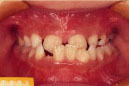

治療前後の比較

受け口

出っ歯

乱抗歯

開咬